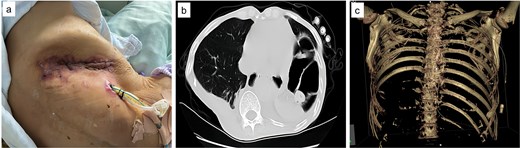

Upon admission, chest computed tomography (CT) and gastroscopy confirmed persistent esophagopleural fistula and empyema (Fig. 1a-c). A multidisciplinary team formulated a stepwise management plan: Stage 1: Under CT guidance, a chest drainage tube was reinserted. The nutrition team optimized nutritional status, correcting hypoalbuminemia and anemia. Thoracic drainage fluid culture revealed multidrug-resistant Pseudomonas aeruginosa; based on antimicrobial committee advice, local treatment (twice-daily 250-ml saline irrigation) was prioritized over systemic antibiotics. Stage 2: After 1 month, the drainage fluid became clearly transparent. However, CT showed unchanged fistula and cavity (Fig. 2a). Thus, a surgical plan was developed. CT-based three-dimensional reconstruction (Fig. 2b-d) guided surgery. Under general anesthesia, a 15-cm incision was made over the 10th rib. The latissimus dorsi muscle flap was dissected with preserved blood supply (Fig. 3a). Intercostal structures were preserved. The 9th and 10th ribs were transected 2 cm from the purulent cavity margin; the 11th and 12th ribs, 2 cm from the vertebral column. After thorough irrigation, a washable drainage tube was placed with its distal end toward the fistula. Muscle flaps were inserted into the cavity and sutured with antibacterial Vicryl (Fig. 3b and c). Finally, the incision was sutured (Fig. 3d). Stage 3: Skin depressions were compressed with cotton pads and a chest strap for 2 weeks (Fig. 4a). Sensitive antibiotics were administered for 2 weeks; intermittent saline irrigation-maintained drainage patency. The drain was removed at 3 weeks. Postoperative CT showed satisfactory recovery (Fig. 4b and c); the duodenal tube was removed 1 month later, and the patient resumed a normal diet gradually. As of July 2025, he remained symptom-free with no recurrence.

Preoperative CT and 3D reconstruction images. (a) CT revealed that the fistula and associated cavity remained unchanged. (b) 3D reconstruction provides a comprehensive visualization of the fistula and its associated cavity. (c) Demonstration of the details, we can see the fistula (arrow), empyema, nasal tube, and drainage tubes. (d), 3D reconstruction including bones, the 10th rib is situated at the center of the abscess, and accordingly, the extent and number of rib dissections are determined based on this anatomical reference.